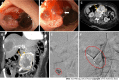

Non-variceal upper gastrointestinal bleeding (NVUGIB) is a common gastroenterological emergency associated with significant morbidity and mortality. Gastroenterologists and other involved clinicians are generally assisted by international guidelines in its management. However, NVUGIB due to peptic ulcer disease only is mainly addressed by current guidelines, with upper gastrointestinal endoscopy being recommended as the gold standard modality for both diagnosis and treatment. Conversely, the management of rare and extraordinary rare causes of NVUGIB is not covered by current guidelines. Given they are frequently life-threatening conditions, all the involved clinicians, that is emergency physicians, diagnostic and interventional radiologists, surgeons, in addition obviously to gastroenterologists, should be aware of and familiar with their management. Indeed, they typically require a prompt diagnosis and treatment, engaging a dedicated, patient-tailored, multidisciplinary team approach. The aim of our review was to extensively summarize the current evidence with regard to the management of rare and extraordinary rare causes of NVUGIB.